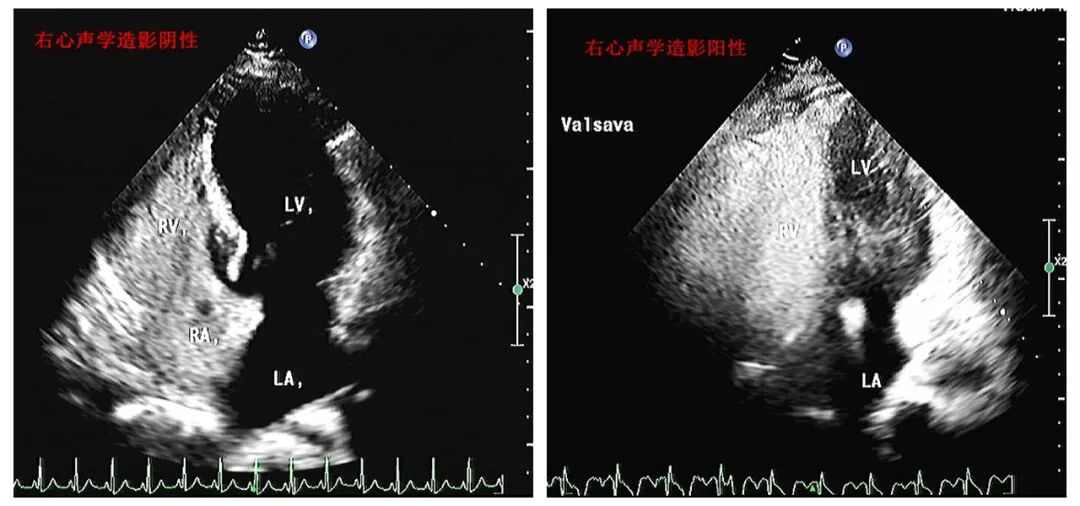

3、右心声学造影

以微泡为“眼”,探查心脏隐秘分流,溯源不明原因卒中与头痛。右心声学造影技术通过经外周静脉注入微泡造影剂,借助超声实时观察微泡在心腔内的显影顺序及分布特征,精准识别卵圆孔未闭、房间隔缺损等右向左分流性病变。该技术对隐源性脑卒中、顽固性偏头痛、减压病等疾病的病因筛查具有重要诊断价值,为临床制定针对性治疗方案提供关键依据。